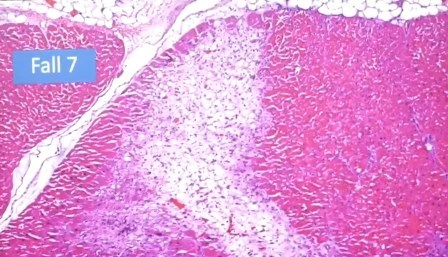

Pulmón

Daño alveolar difuso, no es alveolitis. Sólo se ven los linfocitos por el colapso

Aglomeración de linfocitos alrededor de un vaso

Incluso se ven los folículos, no deberían estar allí porque solo deberían estar en una reacción alérgica y aquí no hay nada exógeno, es endógeno